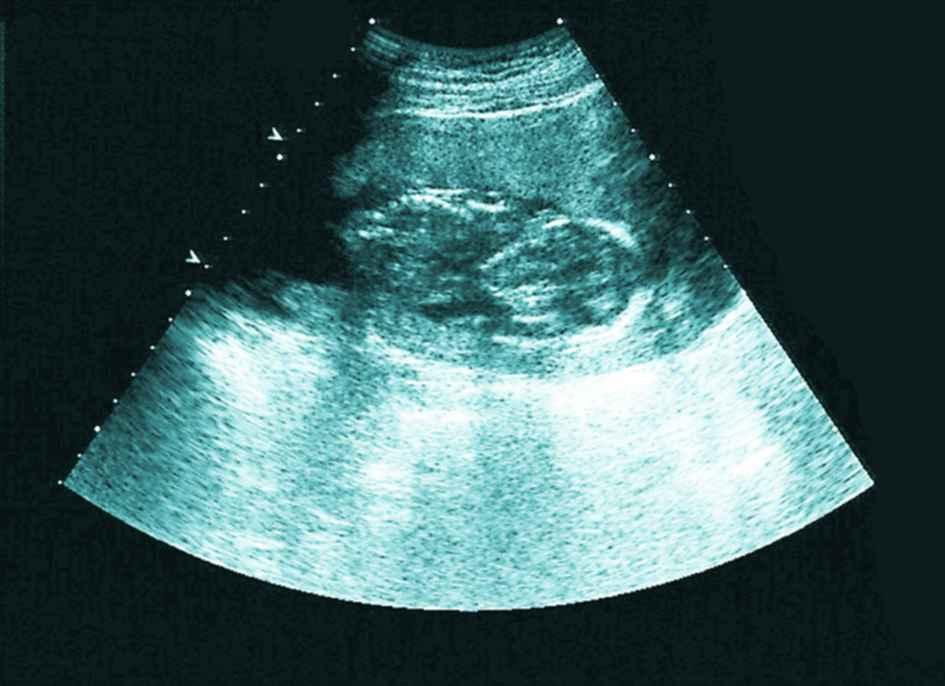

12月迟迟白带不拉丝,以为不会排卵了,到医院做了内诊和B超,又开消炎药,嘱咐我月经后通液或者造影。当时B超结果显示输卵管有优势卵泡16×14,于是回来安排功课了,没有避孕,后来几次避孕。

然而神奇的是,月经日居然测到了亲妈灰,但是颜色加深比较慢,第35天医院B超验血,没检查到孕囊,当时大夫说腹部超看不到宫外,弄得我特烦,跟他顶了几句嘴,血值hcg80不太理想,74小单位的孕酮,7天后hcg700多,又过两天hcg1044,孕酮38,也就是说在第45天,孕酮降落,于是主动B超,结果显示内膜比第35天时的薄了,且回声不均匀,宫内外都没有孕囊,大夫说孕酮降落估计是胎停,因为看不到宫内所以不给保胎。

等到能看到宫内时hcg2800多,孕酮10多一点,被宣布胎停。

孕早期,hcg数值不好,也看不到孕囊,那也不用急躁,关注看B超单,如果内膜不均匀应该是宫内孕,我在网上查阅过有姐妹这么说的,这也是我判断我不是宫外的依据。